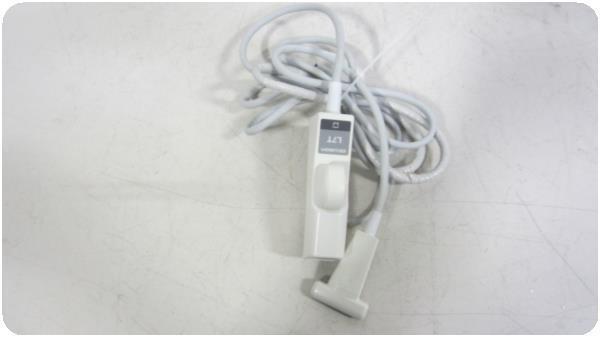

Acuson Linear Ultrasound Probe 7L3 08267217

Sale price$ 3,837.58